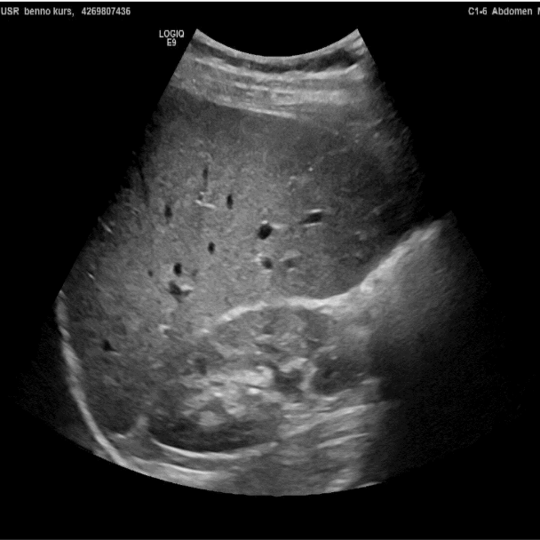

In comparison to other imaging techniques, ultrasound has relatively low technical requirements. Therefore, it can be utilised for clinical evaluation wherever the patient is being treated. This eliminates high costs and logistical constraints and professional diagnostics can be offered to the broad, financially disadvantaged rural population. Point-Of-Care-Ultrasound (POCUS) is used by clinicians to answer a specific clinical question to direct patient care and management. POCUS is relatively easy to learn and can be performed using standardised protocols, with findings being highly recognisable. In addition to the confirmation of an acutely treatable diagnosis, there is thus also a low-threshold and cost-effective initial assessment of the patient.

POCUS can be used for infectious diseases such as pneumonia, tuberculosis or schistosomiasis, as well as for non-communicable diseases such as cancer and liver cirrhosis or emergencies such as heart failure or trauma. Using POCUS can rapidly narrow differential diagnosis, shorten time to definitive treatment, reduce failure and complication rates during procedures and improve patient satisfaction. POCUS is therefore a relevant innovation and serves to optimise medical care for the financially disadvantaged population.